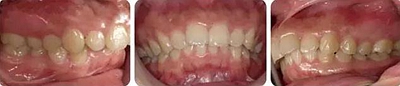

女性,24歲,主訴牙列不齊,面型突。

開唇露齒,閉口時唇肌緊張,反笑線,突面型。

上下牙列輕度擁擠,牙弓偏尖圓形;前牙深覆合深覆蓋;雙側(cè)磨牙尖牙偏遠中關(guān)系。